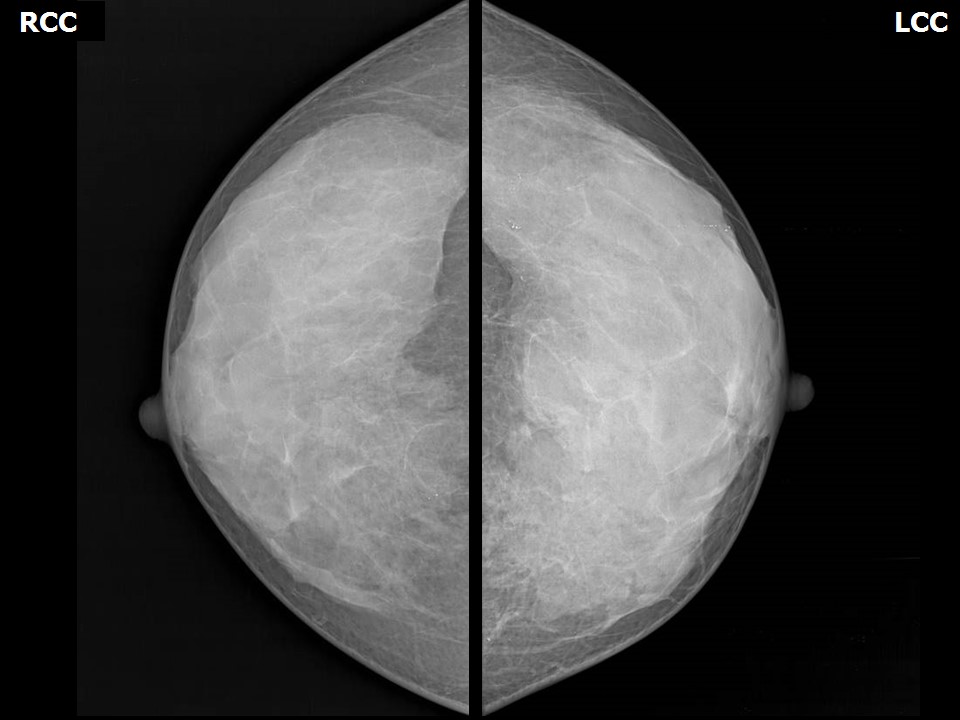

Что такое маммография: важность, процесс и результаты

Раздел: Необычные решения